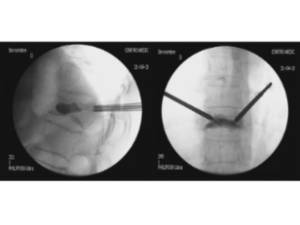

Percutaneous stabilization of unstable vertebral fractures

In cases of complex (unstable, burst, etc.) vertebral fractures, additional stabilization of the fracture by percutaneous stabilization is usually required. In cases where there also is a neurological deficit (muscle weakness, tingling in legs or arms, etc.), a decompression of the spinal canal is additionally required. A percutaneous stabilization of the spine with screws and rods discharges the load on the unstable fracture, stabilizing the whole spine and relieving pain. Depending on the patient’s bone quality, the stabilized vertebrae may be additionally cemented by kyphoplasty.